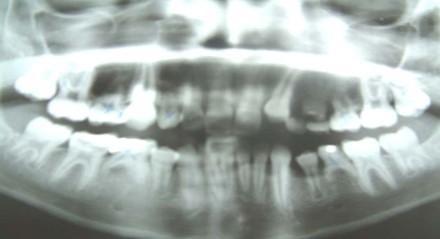

Tερηδόνες θηλασμού (nursing bottle caries)

Στα ροφήματα με μπιμπερό φρόνιμο είναι να μην βάζουμε ζάχαρη, όπως επίσης να μην κοιμάται το παιδί με ζαχαρούχο διάλυμα στο μπιμπερό. Αποφεύγουμε έτσι τη δημιουργία τερηδόνων θηλασμού